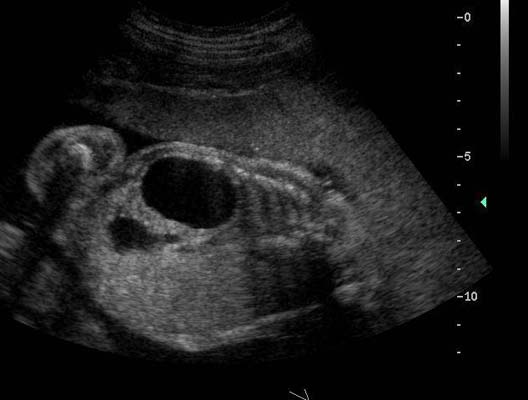

Anéchogène ovalaire